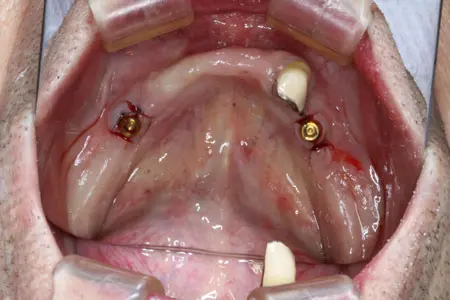

2025.10.0290代男性「他院にて下顎作製したが合わず痛い。食事がとれない。」下顎の前歯部にインプラントを2本埋入し、しっかりと噛めるようになった症例